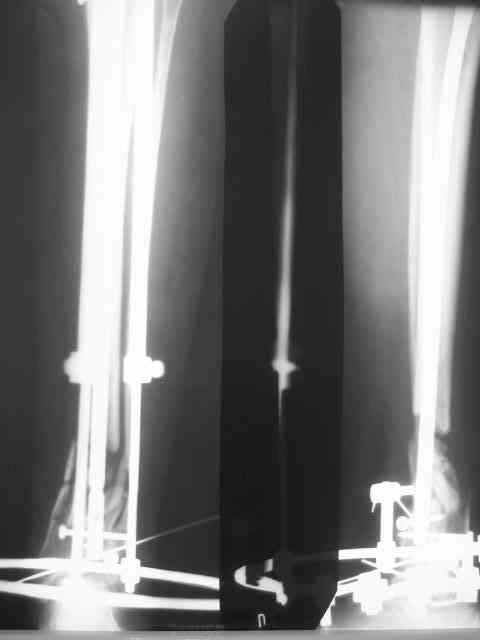

Из истории выяснилось: травма 29.01.07 Диагноз: Открытый оскольчатый перелом н/3 костей голени (якобы 2 Б Каплан), при поступлении операция из трех букв и скелетное вытяжение + остальная терапия. Затем выполнили остеосинтез штифтом (походу Эксперт стоит) видимо хотели зацепится за дистальный отломок, но скорей всего все было нестабильно и накинули этот сокращенный АВФ. На сегодня (162 дня): Больная ходит с ограниченной нагрузкой на конечность (трость). Движения в г/стопе качательные. Трофика мягких тканей не настораживает. Воспаления м/тканей нет.В планах: 1. удаление штифта 2.Наложение стандартного АВФ с фиксацией стопы и устранение всех смещений 3.Резекция нежизнеспособных костных отломков 4.Остеотомия в/3 большеберцовой кости с последующей дистракцией и замещением дефекта.Хотелось бы выслушать мнение по этому случаю!Возможен ли вариант если на опер.столе удастся устранить смещения одномоментной репозицией АВФ и не удалять штифт а производить транспорт большеберцовой кости на штифте? И стоит ли при таком коротком дистальном отломке пытаться блокировать в низу (имеется в виду в АВФ)Спасибо.

Уважаемый коллега, на счет того,что надо интрамедулярный штифт надо убрать, это однозначно, так как большой диастаз между отломками,перелом не срастется, а АПФ фиксировать дистальный отломок очень трудно и будет нестабильность,я бы сделал мостовидный остеосинтез метафизарной пластиной с блокированием, с декортикацией и замещением дефекта аутокостью или другими трансплантатами, и соотвественно остеотомия малоберцовой кости в с/3 или в/3

Пожалуй. Хотелось бы посмотреть на прицельный сниомк дистального отдела голени. Похоже, эпиметафиз смещен кпереди, и с гвоздем внутри это не исправить.

Не вижу необходимости в фиксации стопы. И дистальный отломок tibia достаточно велик, чтобы ввести в него 3-4 спицы с упорами. И голеностопный сустав уже давно пора мобилизовать, дальнейшая фиксация может кончится фиброзным анкилозом.